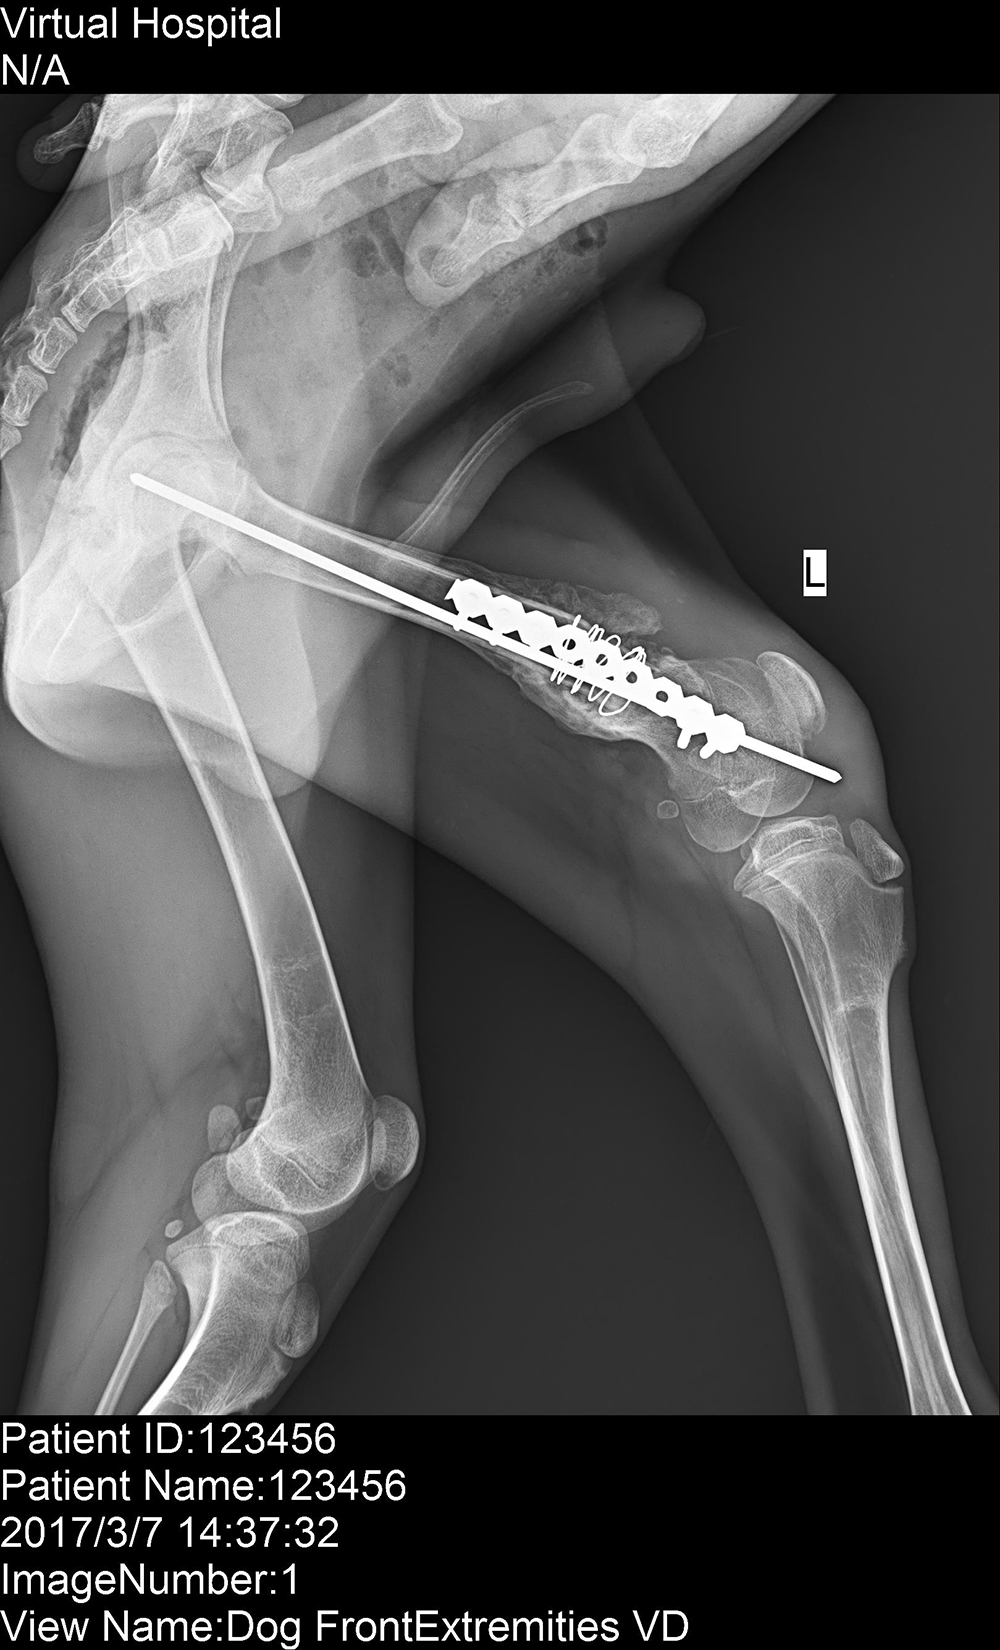

北京芭比堂動物醫(yī)院順軼分院

2017/3/9